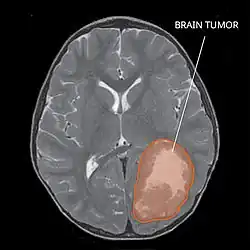

Primitive neuroectodermal tumor of the central nervous system in a 5-year-old

A central nervous system primitive neuroectodermal tumor, often abbreviated as PNET, supratentorial PNET, or CNS-PNET,[1] is one of the 3 types of embryonal central nervous system tumors (medulloblastoma, atypical teratoid rhabdoid tumor, and PNET).[2] It is considered an embryonal tumor because it arises from cells partially differentiated or still undifferentiated from birth.[1] Those cells are usually neuroepithelial cells,[1][2][3] stem cells destined to turn into glia or neurons.[4] It can occur anywhere within the spinal cord and cerebrum and can have multiple sites of origins, with a high probability of metastasis through cerebrospinal fluid (CSF).[1][2]

PNET has five subtypes of tumors: neuroblastoma, ganglioneuroblastoma, medulloepithelioma, ependymoblastoma, and not otherwise specified PNET.[1] It is similar to medulloblastoma regarding histology but different regarding genetic factors and tumor site. It is a rare disease occurring mostly among children,[1][2] accounting for 1.9 to 7% of childhood brain tumors.[2] Symptoms involve emotional, visual, motor, and speech defects.[2] Magnetic resonance imaging (MRI) and computed tomography (CT) are used to diagnose PNETs.[2] Even though a universal treatment plan hasn't been stablished yet, common strategies involve chemotherapy and radiotherapy for individuals older than 3 years of age.[1][2] Their efficacy, however, is still controversial.[2] Surgery can be used to remove mass affected by tumorous cells.[2] The prognosis of the disease is more positive for adults than for children, who have a higher probability of having sequelae from the tumor.[1][2]